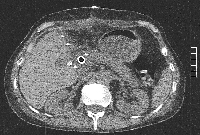

Πρόκειται για γυναίκα ασθενή 56 ετών η οποία, στα πλαίσια διερεύνησης αποφρακτικού ικτέρου, διαπιστώθηκε ότι έπασχε από μονήρες ενδοηπατικό χολαγγειοκαρκίνωμα μεγέθους 7,5 cm που οποίο καταλάμβανε τα τμήματα 1, 2, 3, 4a, 4b, 5 (μερικώς) και 8 (μερικώς), διηθούσε την αριστερή και τη μέση ηπατική φλέβα, είχε προκαλέσει θρόμβωση του αριστερού κλάδου της πυλαίας φλέβας και εφίππευε στο δεξιό κλάδο της πυλαίας φλέβας (εικόνα 1). Η άρση της χολόστασης προεγχειρητικά επιτεύχθηκε με ERCP και τοποθέτηση stent δεξιού χοληδόχου πόρου. Πραγματοποιήθηκε προεγχειρητική ηπατική ογκομέτρηση με ανάλυση MeVis (εικόνα 2). Διεγχειρητικά εξασφαλίστηκε η δυνατότητα ολικού αγγειακού αποκλεισμού (εικόνα 3). Διενεργήθηκε αριστερή εκτεταμμένη ηπατεκτομή. Ο όγκος αφαιρέθηκε πλήρως, με άθικτη κάψα (εικόνα 4). Το ηπατικό υπόλειμμα ανήλθε στο 31% του αρχικού όγκου του οργάνου (εικόνα 5). Η ογκομετρική CT την 4η μετεγχειρητική εβδομάδα ήταν ικανοποιητική (εικόνα 6). Η ασθενής πήρε εξιτήριο την 7η μετεγχειρητική ημέρα. Έλαβε μετεγχειρητική χημειοθεραπεία (GEMOX).